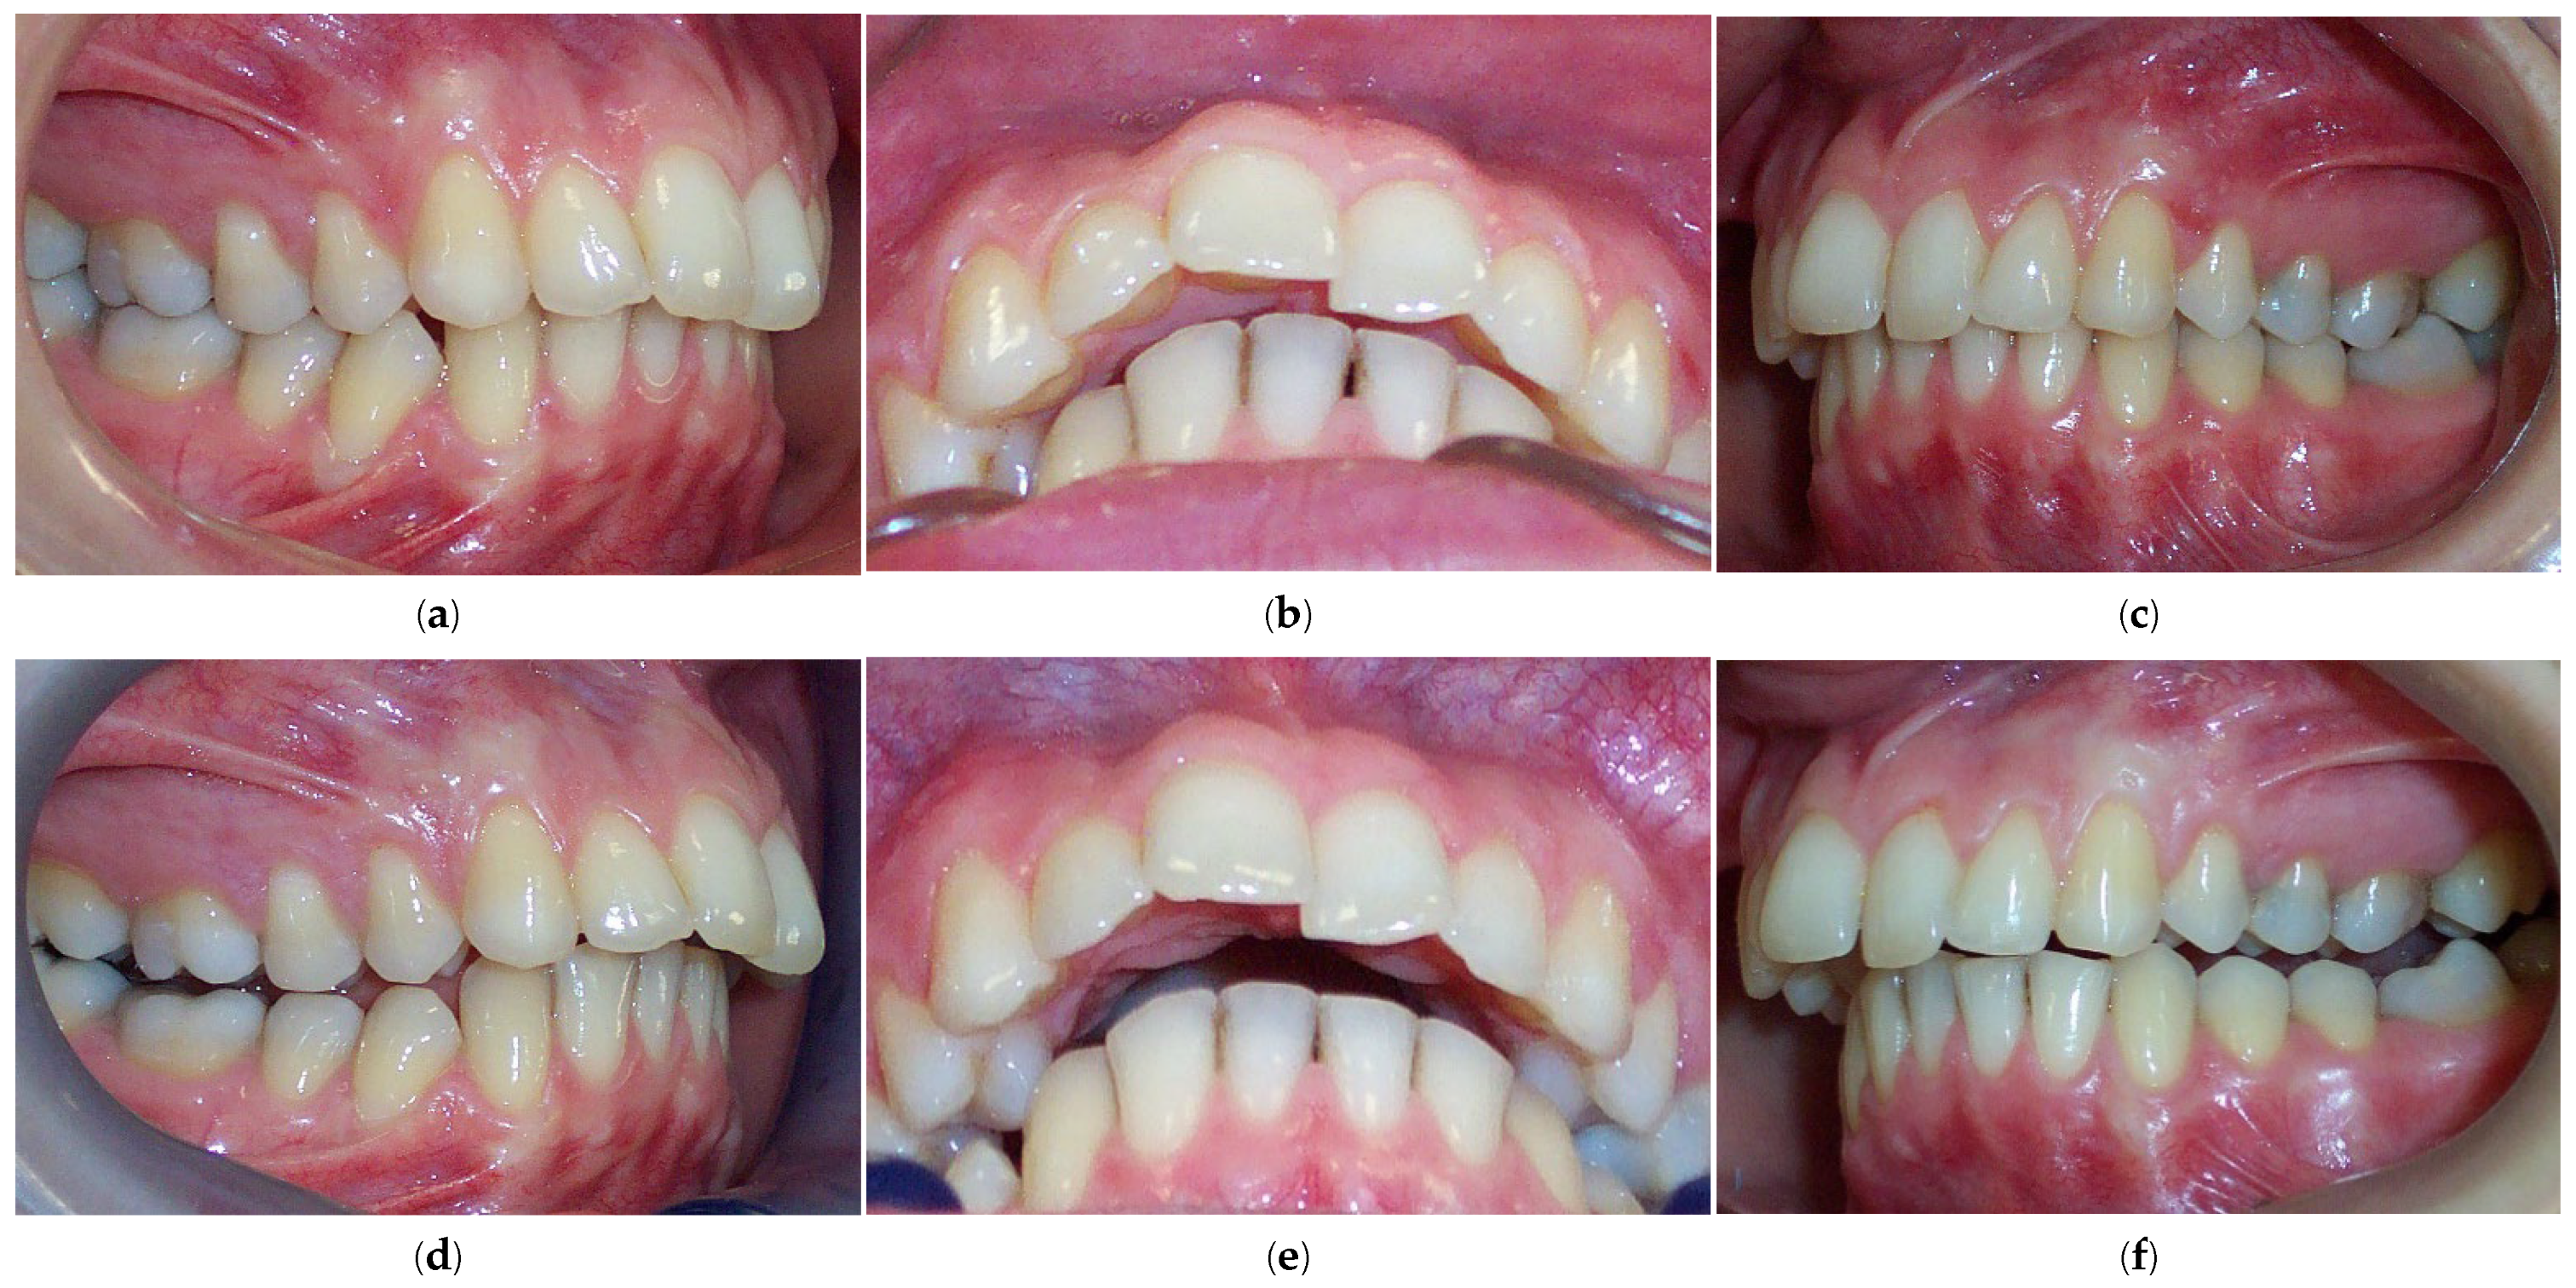

2. Materials and Methods

2.1. Subjects

3. Results